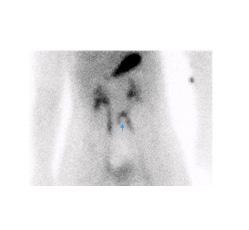

Figure 3 : Patient de 2 ans avec rectorragies intermittente depuis 7 mois et anémie. Examen effectué avec préparation pharmacologique de type ranitidine per os. Étude dynamique ( A ) et statique ( B ) en incidence antérieure démontrant un foyer pouvant potentiellement être d’origine rénale au niveau de l’hypochondre droit (flèche). Position antérieure du foyer de captation démontré par l’incidence latérale droite (C) et confirmé par la triangulation en SPECT ( D) et le rendu 3D (E). Mise en évidence d’un diverticule de 2cm contenant de la muqueuse gastrique ulcérée et de la muqueuse pancréatique.

Interprétation

Le diverticule de Meckel apparait comme une captation focale le plus souvent au quadrant inférieur droit (figure 8). La captation apparait souvent dans les 5 à 10 minutes après l’injection en parallèle avec l’estomac et peut apparaitre dès la première minute. La captation augmente en intensité avec le temps, typiquement au même rythme que la captation gastrique alors que l’activité rénale démontrée dans les 2-3 premières minutes va diminuer (figure 9).